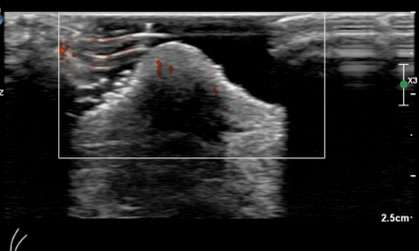

Case: Paget's Disease Figure 3

Figure 3: Contrast enhanced breast MRI demonstrates abnormal enhancement of the left nipple and areola, consistent with biopsy-proven Paget’s disease of the breast.